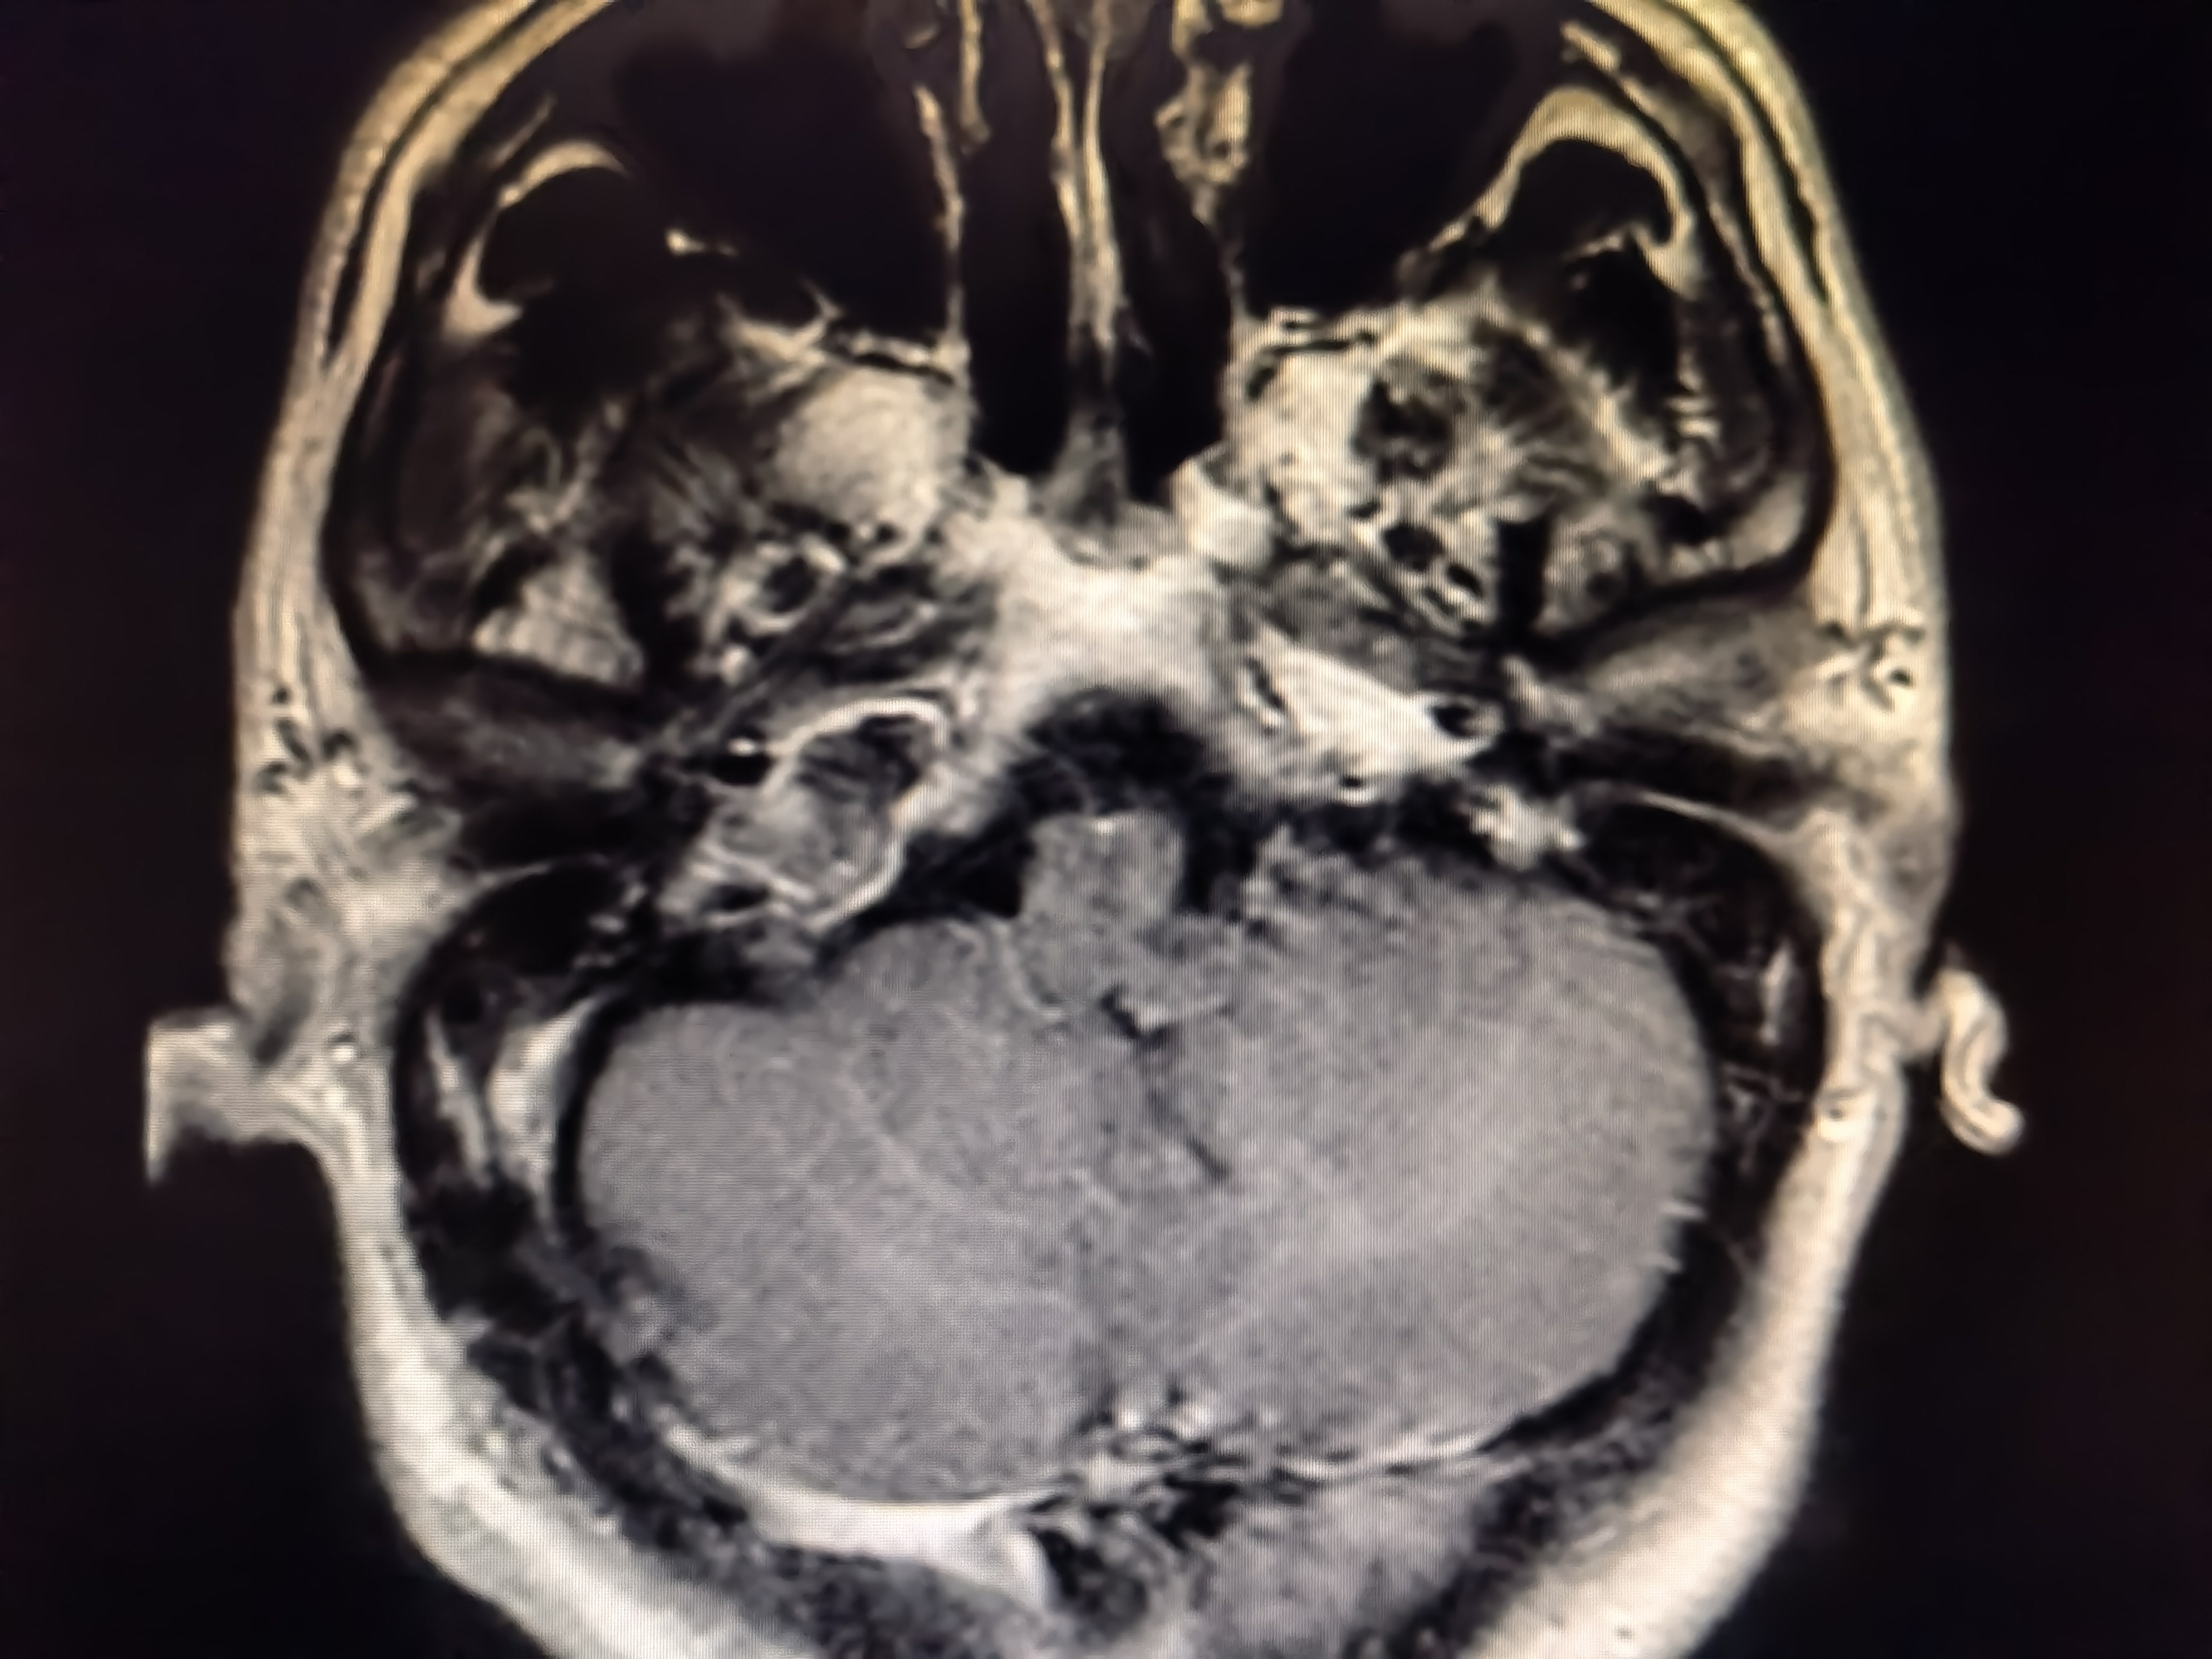

术前磁共振